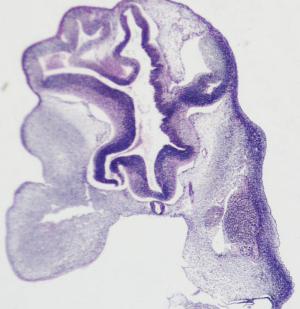

Stage 16

CfS 16

d29-30